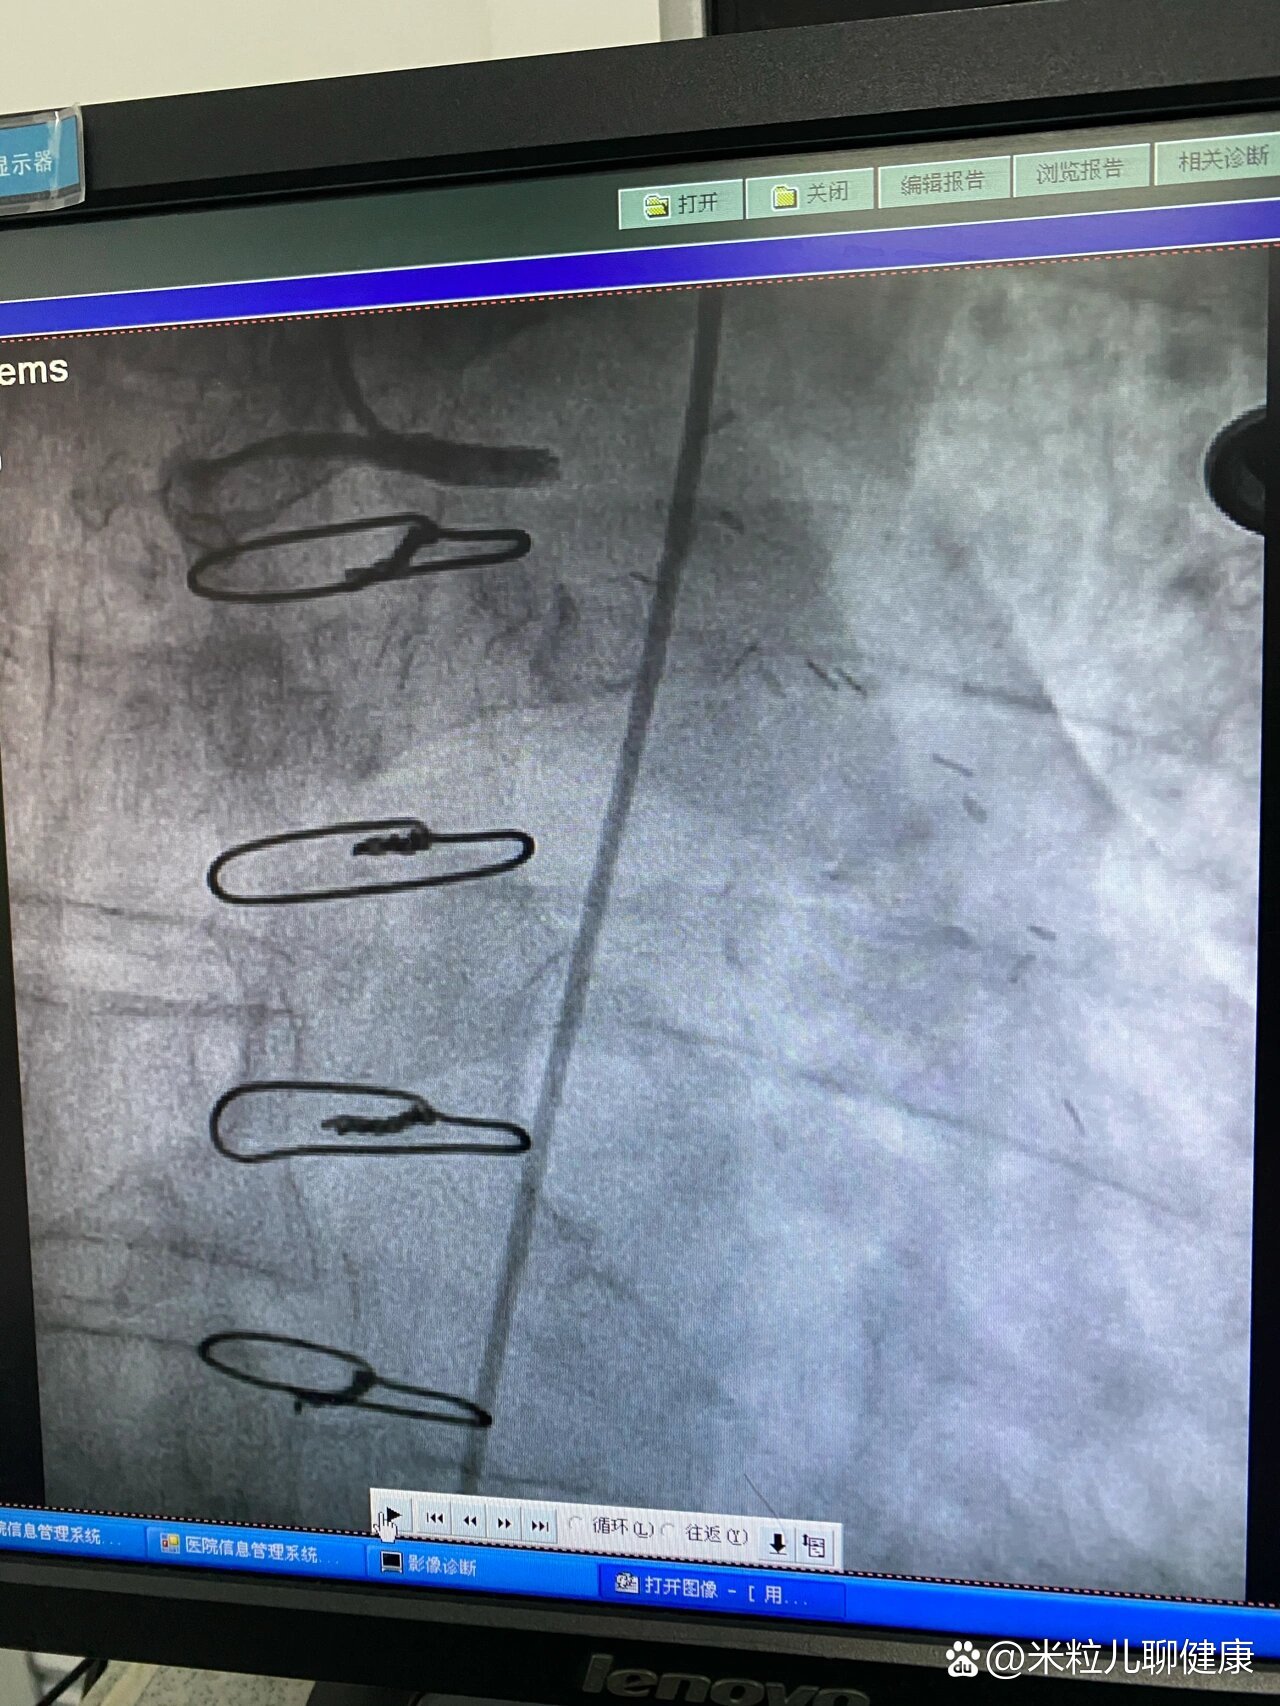

石" 闽东医院心内科开展首例经皮冠状动脉腔内冲击波球囊导管成形术

哈医大四院心内八病房巧用震波球囊治疗冠脉狭窄又钙化